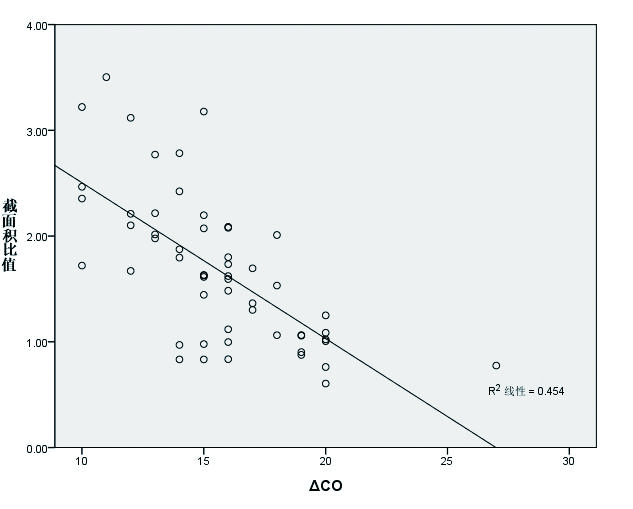

2.4 IJV/CCA截面积比值容量反应阳性组IJV/CCA截面积比值(1.38±0.55)明显小于容量反应阴性组截面积比值(2.16±0.68),差异有统计学意义(t=-4.66,P < 0.001)。IJV/CCA截面积比值为(1.68±0.71)mm,IJV/CCA截面积比值与PLR试验引起的ΔCO值有显著相关性(r=-0.67,n=55,P < 0.01)(图 5)。应用ROC曲线评价IJV/CCA截面积比值与PLR试验引起的ΔCO值, 其曲线下面积为0.823(95% CI: 0.703~0.943),相应阈值为1.65(灵敏度86.4%,特异度78.8%)(图 6)。

|

| 图 5 IJV/CCA截面积比值与ΔCO值呈显著负相关性 Figure 5 A significant negative correlation between the ratio of IJV/CCA cross-sectional area and ΔCO value |

国内外大量文献证实,PLR试验能够预测重症患者的容量反应性[10-13]。一项Mate分析提示PLR联合ΔCO能够准确评估患者容量反应性,其灵敏度和特异度分别是89.4%和91.4%[14]。有研究显示,超声测得的CO和PiCCO获取的CO具有显著的相关性(r=0.97,P < 0.01),说明超声评估容量状态具有较高的准确性[15]。但是PLR试验不仅耗时、耗力,而且受诸多因素限制,因此数据获取率和准确性较高的评估方法极为需要。颈部有双侧血管,超声影像数据极易获取,数据测量不易受病情危重程度等因素限制。此外,IJV/CCA截面积比值从一定程度上消除了颈部血管个体差异的影响。

本研究发现IJV/CCA截面积比值与PLR试验引起的ΔCO值评估容量反应性有相关性,其灵敏度86.4%,特异度78.8%。同时,IJV直径、截面积与ΔCO值也存在较弱的相关性。说明IJV/CCA截面积比值评估容量反应性比IJV直径、截面积更可靠;此外,本研究发现CCA直径与截面积不适合评估容量状态。